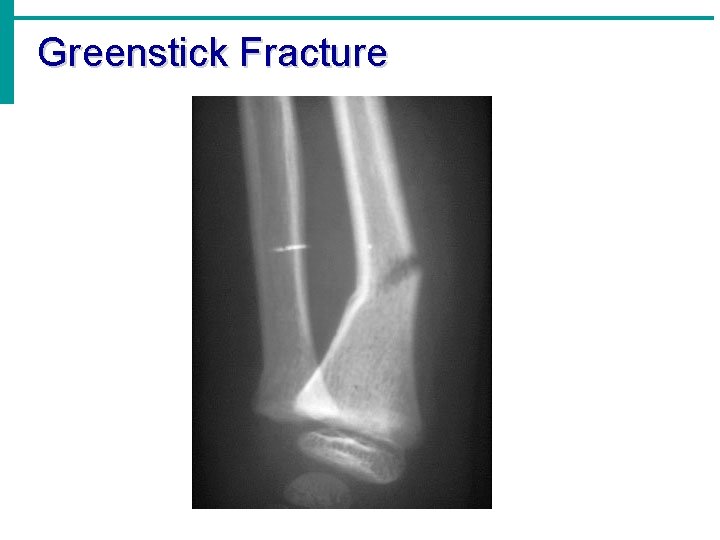

Greenstick Fracture